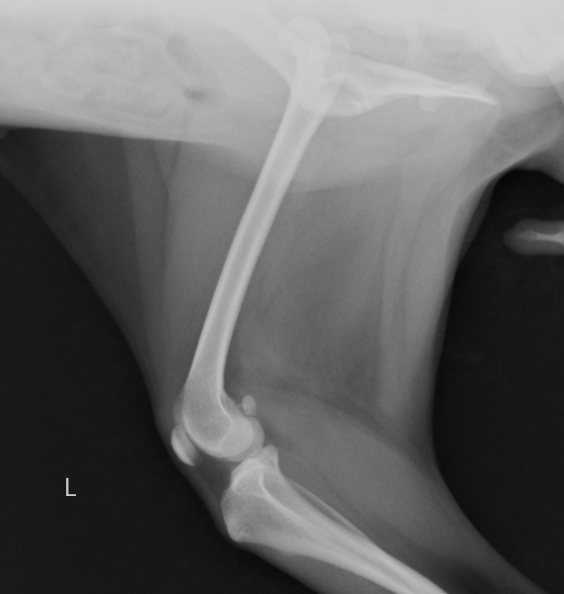

今回はトグルピン法という方法でもとに戻した症例です。症例はトイプードル10ヶ月で、ジャンプしているうちに足を痛がって挙げているとのことで来院されました。レントゲンで前上方脱臼が認められ手術を行いました。

大腿骨頭と呼ばれる部分が前方に脱臼しています

大腿骨頭が上方に脱臼しています